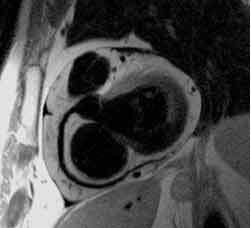

MR-Angiographie

Die MR-Angiographie erlaubt die Darstellung der Schlagadern sämtlicher Blutgefäßregionen und hat in der Diagnostik die DSA verdrängt. Gefäßfehlbildungen, -aussackungen (Aneurysma) und Gefäßverengungen z.B. durch Arterienverkalkung können dargestellt werden.

Lediglich bei der Darstellung der Herzkranzgefäße und bei einigen speziellen Fragestellungen, wo einzelne Gefäße selektiv dargestellt werden müssen, ist eine Katheterangiographie als DSA noch zwingend erforderlich.

MR Angiographie

Im Gegensatz zu den CT-, DSA- und Röntgenuntersuchungen werden aber keine jodhaltigen Kontrastmittel verabreicht, sondern spezielle, wesentlich besser verträgliche MR-Kontrastmittel. Einige Gefäßregionen können sogar ganz ohne Kontrastmittelgabe dargestellt werden. Deshalb kann eine MR-Angiographie auch bei bekannter Allergie gegen Röntgenkontrastmittel ("Jodallergie"), bei Schilddrüsenfunktionstörungen und Nierenfunktionsstörungen durchgeführt werden.

Ein weiterer Vorteil ist, dass schädliche Röntgenstrahlen nicht zur Anwendung kommen. Außerdem ist es nicht erforderlich eine Schlagader zu punktieren und nach der Untersuchung stundenlang flach mit einem Druckverband zu liegen. Da nicht mit Kathetern im Gefäßsystem gearbeitet wird, ist die MR-Angiographie viel risikoärmer.